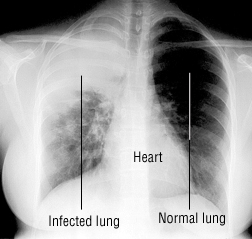

Most people know I wasted pretty much the entire month of July snuggled on the couch with the dog and eating popsicles while I struggled with pneumonia. I started coughing a few days before my road trip, but nothing major. Just an occasional tickle. It continued through my trip and became a bit more persistent the first few days in July. So the 4th of July I went to the Urgent Care clinic, finally ready to admit that it wouldn’t just go away. I got a round of antibiotics and an inhaler and was sent on my way. Even while on the antibiotics, I started getting a bit worse and a few days later ended up with a 103.6 temp (and wondering at what point ones brain begins to melt). I went back in to the clinic and was given another round of antibiotics, prednisone and cough syrup with codeine. And still I got worse. The worst part was that I wasn’t sleeping more than 2-3 hours a night. At the end of my five day antibiotic I woke at 3am and watch NCIS on my phone, in 4B11220bed, until the clinic opened. I finally got a chest x-ray, a few rounds with the nebulizer, a shot of antibiotics to the ass, a shot of steroids to the ass and 10 days of a much stronger antibiotic. That was my docs last try before sending me to the hospital. I lucked out, and within 12 hours of the new meds, the shots, etc, there was a noticeable difference. It’s been three and a half weeks, and it’s only the last two days that I’ve noticed that my lungs don’t make that nasty rattle sound when I breath deep. While sick I was fairly entertained (and disgusted) by using the stethoscope to listen to my lungs. I still cough off/on and will likely be using my inhaler for a while still, but I’m more irritated at missing out on nearly an entire month! I even missed a sounders home game – a clear indicator of how sick I was!